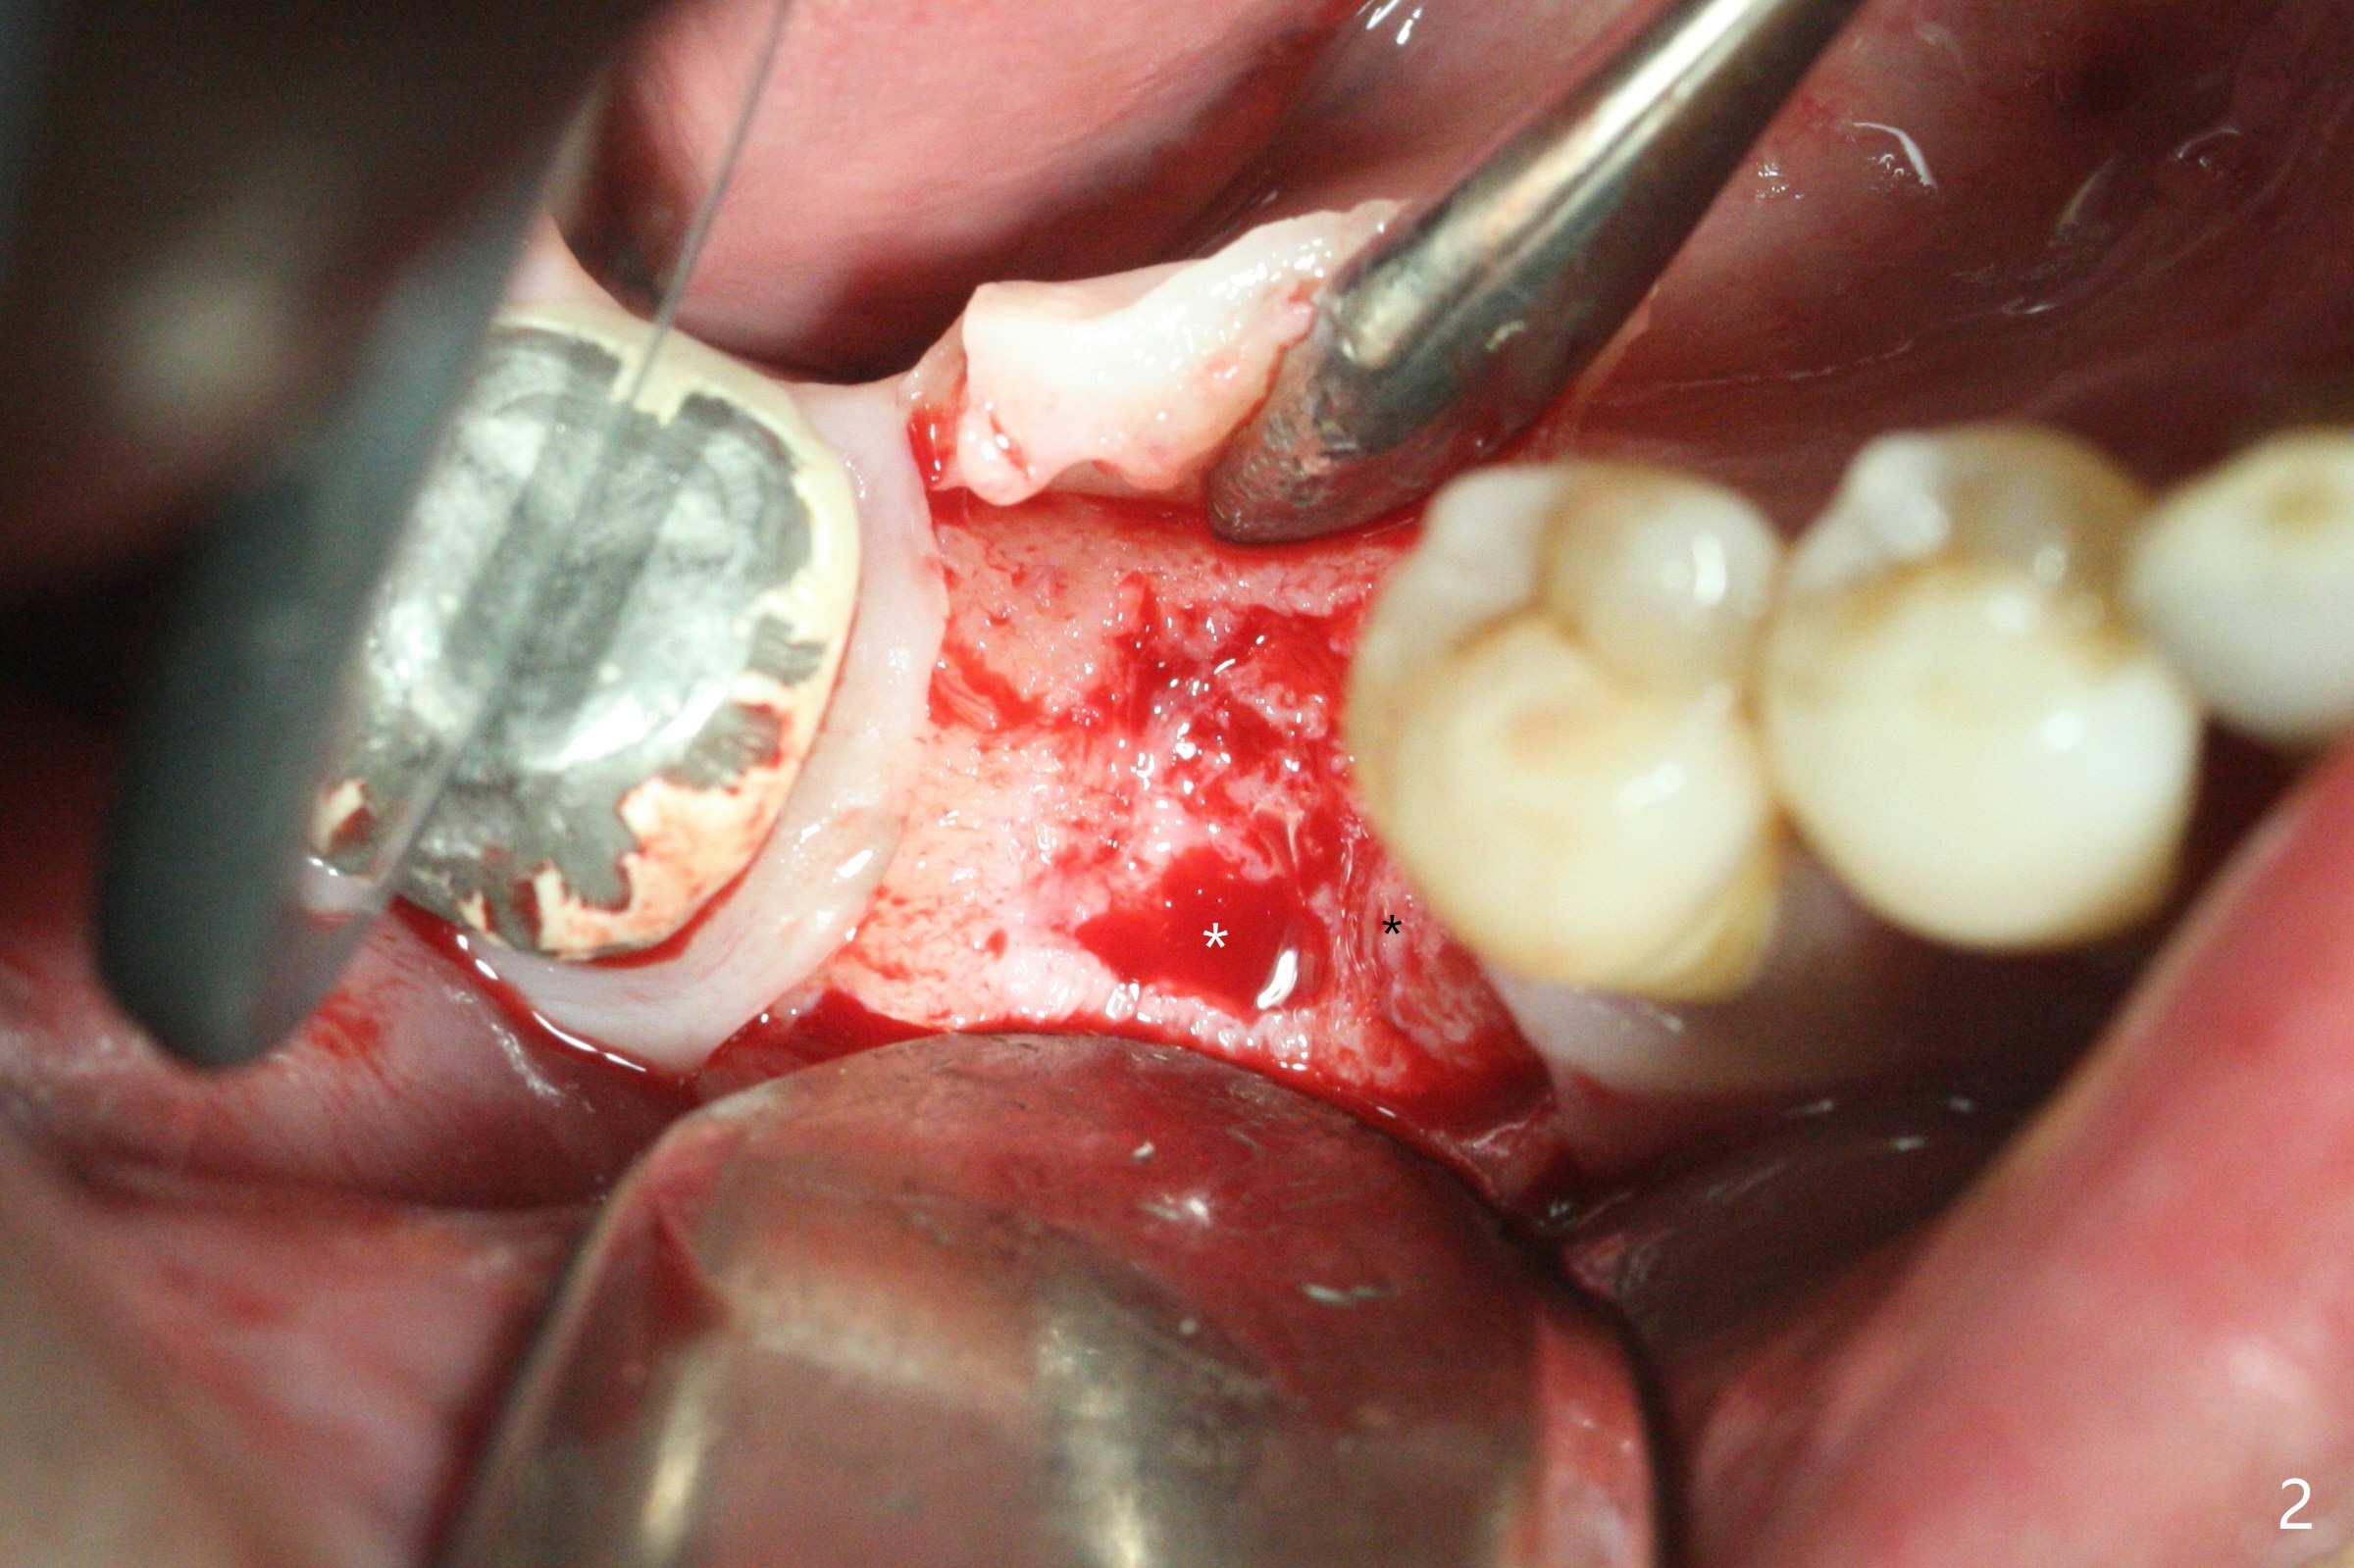

The sockets of #30 (M) of a smoker (M) are apparently not healing ~ 2 months post extraction (Fig.0, 0'). The ridge looks wide 3 months post extraction without bone graft in other office before (Fig.1) and after (Fig.2) flap surgery. The socket appears to have healed perfectly consi-dering buccal defect (M) revealed by CT ~ 1 month earlier. When a 5x10 mm implant is placed with guide and high torque (in spite of overprep), granu-lation tissue is found mesio-buccal (MB, Fig.2 *). After curettage, bone graft is placed around the implant, especially MB (Fig.3 *), followed by PRF. Periodontal dressing dislodged a few days postop because of mastication on the right side (Fig.4), whereas the anterior one (24/26) remains in place. There is a small gap around the implant when it is uncovered (Fig.5 arrowheads). It appears that some of bone graft gets lost from the incision (smoker). A 6.5x5.5(4) mm cemented abutment is seated and torqued at 30 Ncm before impression (Fig.6). There is no bone loss 11 months post cementation (Fig.7).